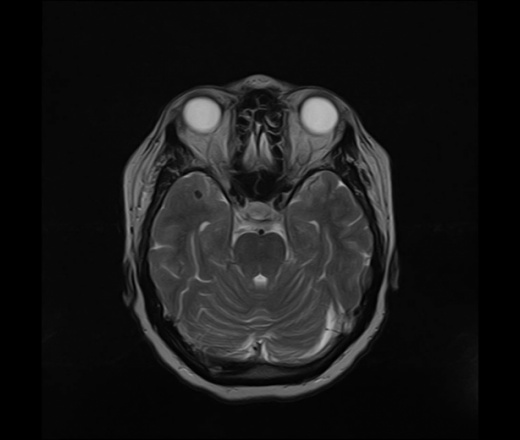

Пациентка 1955 г.р направлена с диагнозом извитость ВСА для исключения очаговых изменений. Это аневризма бифуркации правой средней мозговой артерии (диаметр около 4.5 мм)? Также выпуклый верхний контур гипофиза на корональном срезе - или это место соединения с воронкой гипофиза? Вертикальный размер 5 мм.

Ax T2 ID:61187

По таким снимкам гипофиз оценить можно только примерно, тут мне кажется не стоит придираться. А почему не делали сосуды если тут аневризма?))

Гипофиз нормальный, аневризма-очень даже есть.

Я за аневризму.